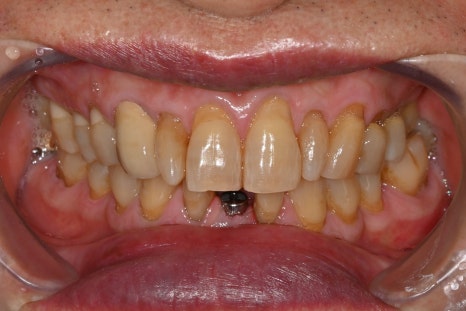

Photo with the final prosthesis placed 3 months after surgery

Three months after surgery, the final prosthesis was also placed,

and all treatment was completed.